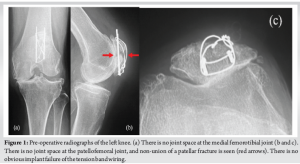

An 85-year-old female visited our hospital complaining of left knee pain. She had undergone ORIF with tension band wiring (TBW) for a left patellar fracture 7 months previously at a different hospital. However, bone union of the patellar fracture had not been achieved and the left knee pain persisted. She had a history of right patellar fracture and fractures of both ankles. Her body mass index was 25.6 kg/m2 (height, 157 cm; weight, 63.0 kg). Because of the left knee pain, she needed support for walking indoors and used a wheelchair outdoors. On physical examination, the range of motion (ROM) of the left knee was 0–120°. The pain was present at the medial joint space and around the patella, where it was particularly severe, with a Numerical Rating Scale (NRS; 0–10) of 8. Both of these areas were tender on palpation. No ligamentous instability was observed. Her Knee Society (KS) knee score was 53, and her KS function score was 40. Bone mineral density of the lumbar spine and proximal femur were 1.305 g/cm² and 0.678 g/cm², respectively. Radiographs of the left knee showed non-union of the patellar fracture, no joint space at the patellofemoral or medial femorotibial joints, and evidence of OA at the level of Kellgren–Lawrence classification stage IV at both of these sites (Fig. 1). Computed tomography (CT) of the left knee also showed non-union at the middle of the patella (Fig. 2). The femorotibial angle was 179°. There was no obvious implant failure of TBW. The diagnosis was severe knee OA with patellar non-union after a previous ORIF. As treatment for the patellar non-union and bone fragility, we initially treated the patient with low-intensity pulsed ultrasound (LIPUS) (Exogen Ultrasound Bone Healing System; Bioventus, Durham, NC) and teriparatide injection (Teribone; Asahi Kasei Pharma, Tokyo, Japan). LIPUS (1.5 MHz) was applied to the affected area for 15 min every day. As there was insufficient improvement in both the subjective symptoms and imaging findings in the left knee after 1 year of treatment, we decided to perform TKA and surgery for non-union of the patella in a one-stage procedure.